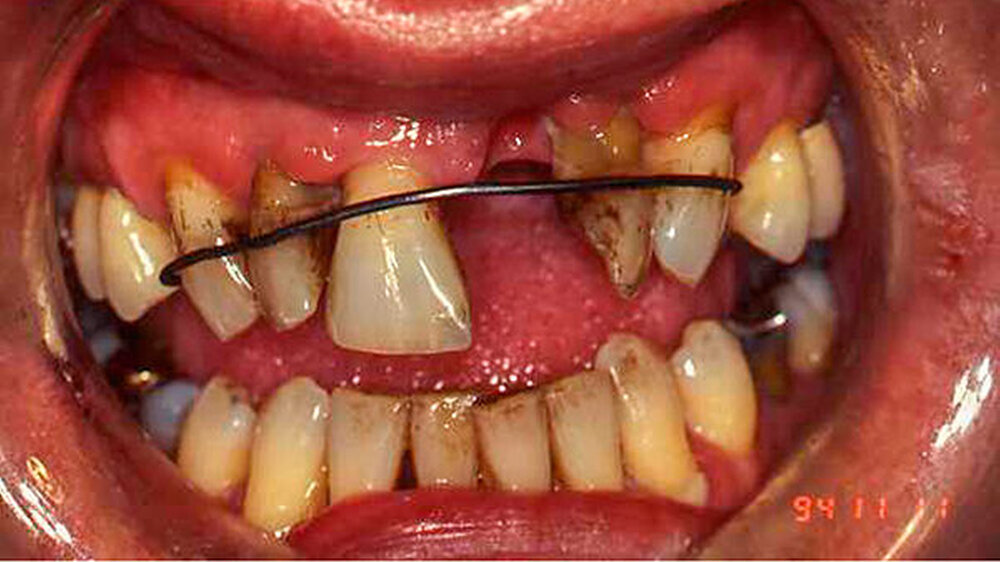

Festgezurrt mit Blumendraht

Dieser Fall wurde eingereicht von Dr. Wilfried Forschner, Köhlestrain 86, in 88400 Biberach

"Die Ausnahmefälle kommen Freitagabend kurz vor Praxisschluss", heißt es oft in Fortbildungen. Genauso ist es. Und wenn nicht, sind es Fälle, die auch nach der Arbeit im Gedächtnis bleiben.